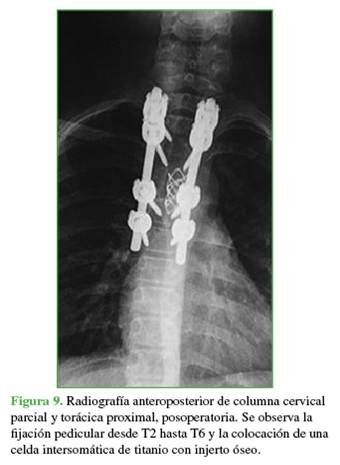

En el segundo tiempo quirúrgico, se procedió a colocar un espaciador de titanio con injerto óseo autólogo (Figura 9).